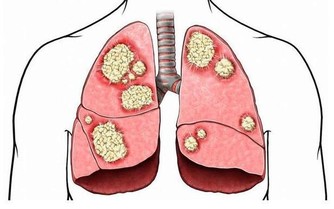

捂熱綜合徵也稱蒙被缺氧綜合徵,是嬰兒在寒冷季節中較為常見的急症之一。

主要原因包括:

①蒙被造成呼吸道受阻,引起嬰兒慢性不全性缺氧;

②過暖、大汗淋漓,造成嬰兒高滲性脫水。

捂熱綜合徵臨床表現以神經系統症狀為主、嚴重者並發呼吸衰竭、腦水腫、休克等多髒器功能衰竭等一系列的臨床症狀。嬰兒捂熱綜合徵患兒病死率高、後遺症嚴重。